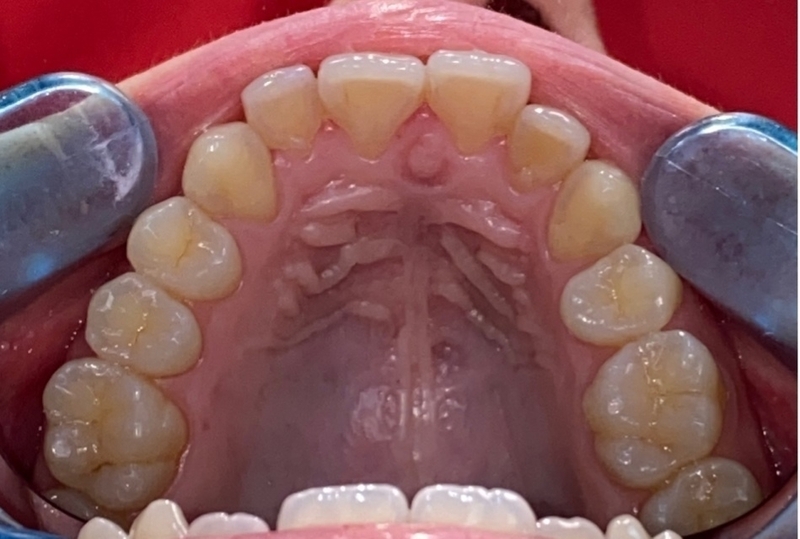

Cas 1 - Parodontie

Avant